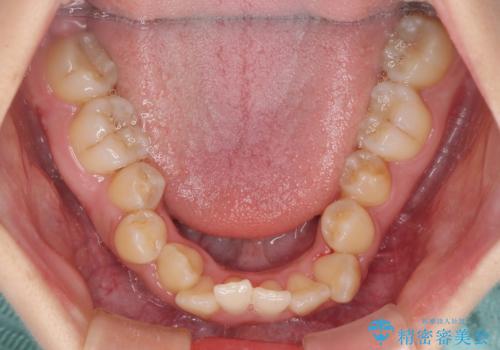

- 前歯の著しい叢生とクロスバイトを気にして来院された患者様です。

叢生が強いため、一見すると抜歯矯正と判断したくなりますが、下顎臼歯が舌側に倒れていることから、上顎骨を側方拡大し、非抜歯矯正の可能性を検討することとしました。

急速拡大装置による上顎骨の側方拡大が思った以上にうまくいき、非抜歯での矯正が可能となりました。

内側に倒れていた下顎の臼歯は起き上がり、清掃性も大幅に改善されました。